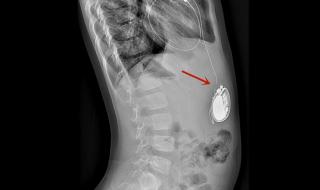

一、全磁浮人工心脏介绍

全磁浮心脏即离心泵人工心脏,被称为第三代人工心脏,是目前最先进,对人体影响最小也是最耐用的人工心脏,美国FDA前两年刚上市了第一款,我国高端医疗器械几乎无国产产品。